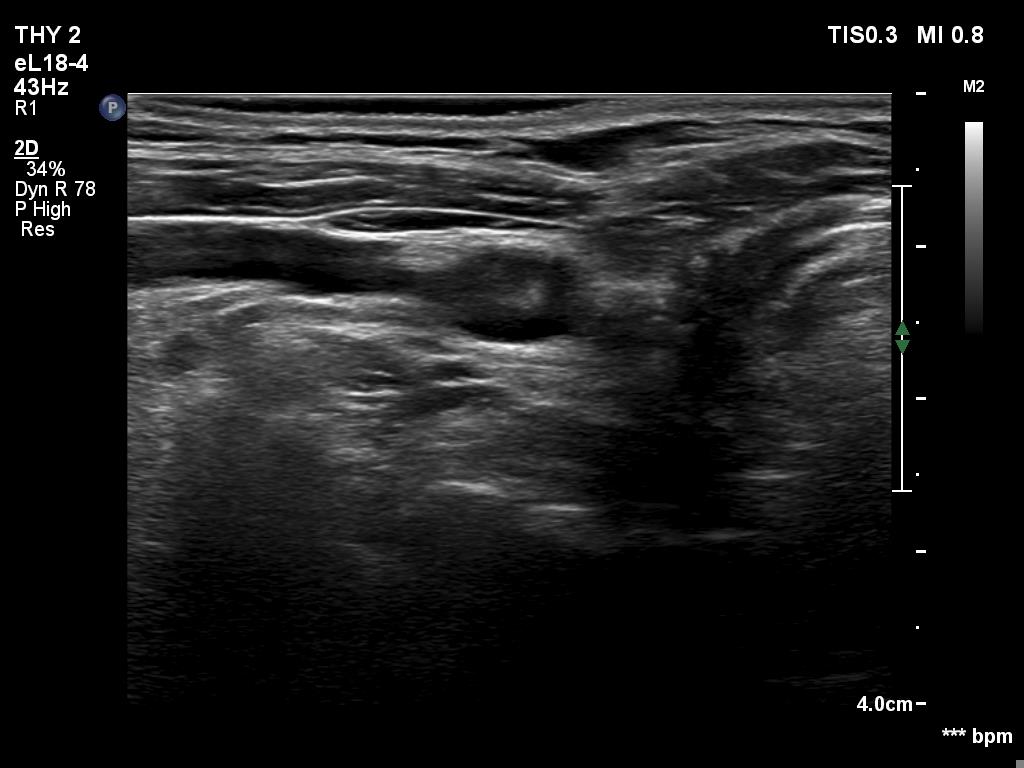

Five years after surgery (fourth row of images):

Clinical data: The patient had no complaints.

Palpation: no abnormality.

Functional test: TSH 1.16 mIU/L on daily 125 microgram levothyroxine.

Ultrasonography. There was minimaly if any thyroid remnant in the thyroid beds. Connective tissue replaced the thyroid.

Suggestion: yearly TSH determination, in the event of pregnancy at once.